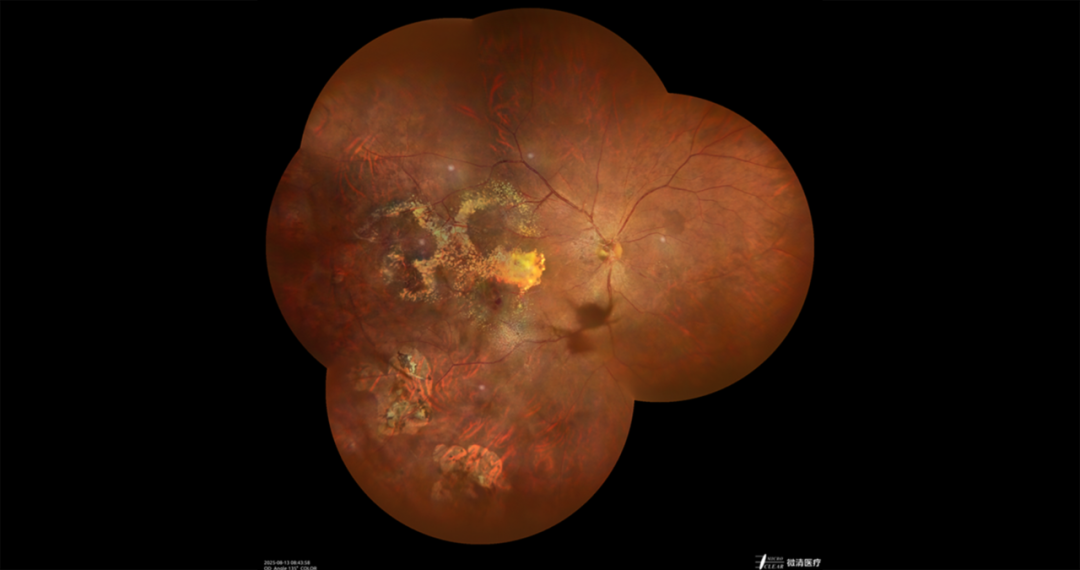

11、Coats/中国人民解放军中部战区总医院

11.png

11(1).png

11(2).png

11(3).png

10(4).png

(1) 患者基本信息:男性,61岁

(2) 主诉:右眼视力下降3年余,加重2月余。

(3) 初步诊断:右眼湿性年龄相关性黄斑病变、右眼视网膜大动脉瘤、右眼coats病。